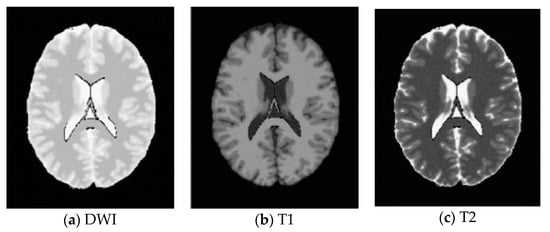

In this work, a DNA-GA optimized Tsallis [21] entropy and kernel SVM have been implemented for the classification of brain tumors as benign or malignant, which is called DNAGA-TE+KSVM. The features used for this approach were the gray matter (GM), white matter (WM) and cerebral spinal fluid (CSF) probability map, which are shown in Figure 1. Adding the WM and CSF to the features can improve the results of the method of grouping voxels into ROIs by packaging labeled atlas. These features are extracted with the help of Discrete Wavelet Transforms (DWT) [22] and Tsallis entropy. The DNA-GA algorithm is used to search a set of good parameter values in the Tsallis entropy and Gaussian radial basis function kernel. The algorithm in this paper can quickly get good parameter values and improve the classification performance of the SVM. The five-fold cross-validation is used to protect the classifier from overfitting. Once the features are extracted they are classified with the help of a trained SVM classifier.

In this paper, we used two types of images. One type of data comes from the Simulated Brain Database (SBD). MRI images can be downloaded from this database. Another kind of image is real an MRI image downloaded from the website of Harvard Medical School. In our experiments, we only retained three main brain tissues, including GM, WM and CSF, but there were skulls and other tissues in the original image.

Figure 1. Distribution of CSF, GM and WM in brain tissues.